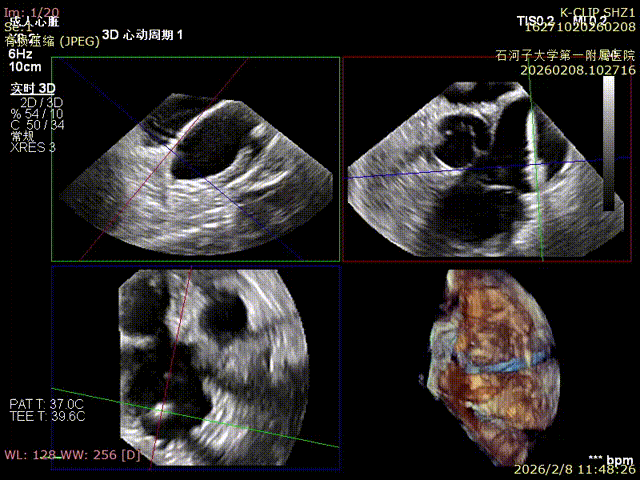

Comparison of preoperative reflux and postoperative reflux

Preoperative

Preoperative reflux

Postoperative

Postoperative reflux

Immediate Postoperative Echocardiographic Assessment: Tricuspid regurgitation was reduced from preoperative grade 4+ to grade 1+, the annulus diameter was reduced to 6.15 cm², and the leaflet coaptation was satisfactory.

Preoperative annulus area: 11.5 cm²

Postoperative annulus area: 6.15 cm²